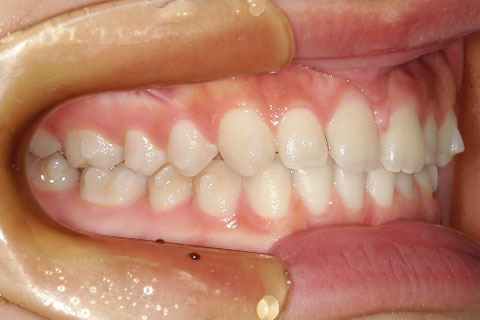

主訴:上下の歯並びのガタガタが気になる

診断名:上下顎叢生

症状:上下顎叢生

患者プロフィール:北九州市・小倉北区30代女性

治療方針:非抜歯治療

治療装置:マウスピース型矯正治療(インビザライン)

抜歯:無し

治療期間:一年半

通院回数:30回

リテーナー:上顎プレートタイプリテーナー 下顎フィクスタイプリテーナー

治療費用:検査診断料(20,000)+装置料金(500,000)+管理調整料(150,000) +装置撤去時診断料(10,000) +保定装置料金(20,000)=700,000(消費税込)

リスク副作用:痛み・治療後の後戻り・歯根吸収・歯髄壊死

詳しい症例説明:この患者さんはガタガタが気になり来院されました。マウスピースタイプの矯正装置で比較的短期間で治療を終えることができました。インビザライン(マウスピース矯正治療)で矯正治療を行うことで取り外して食事ができ、痛みもそれほど感じなかったとのことです。